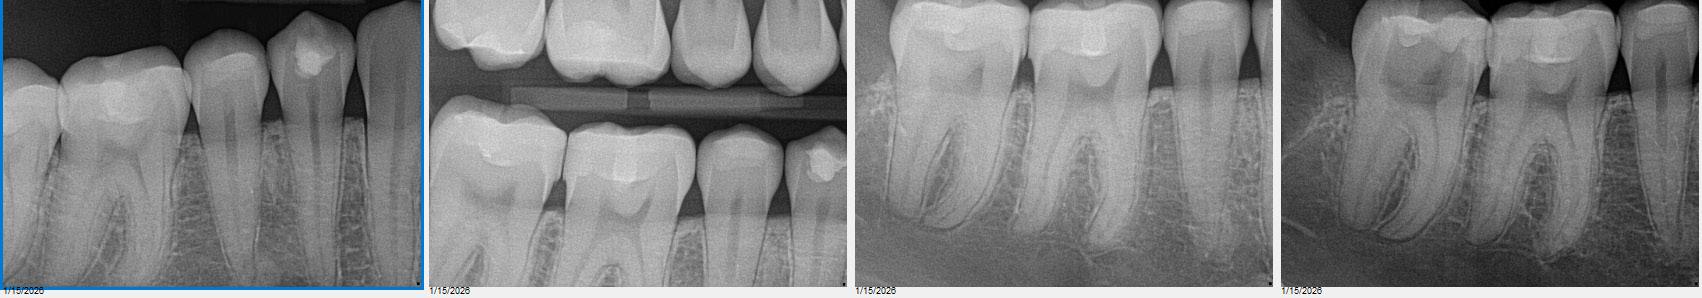

Game: Guess which one of our managing editor's teeth needed a root canal!